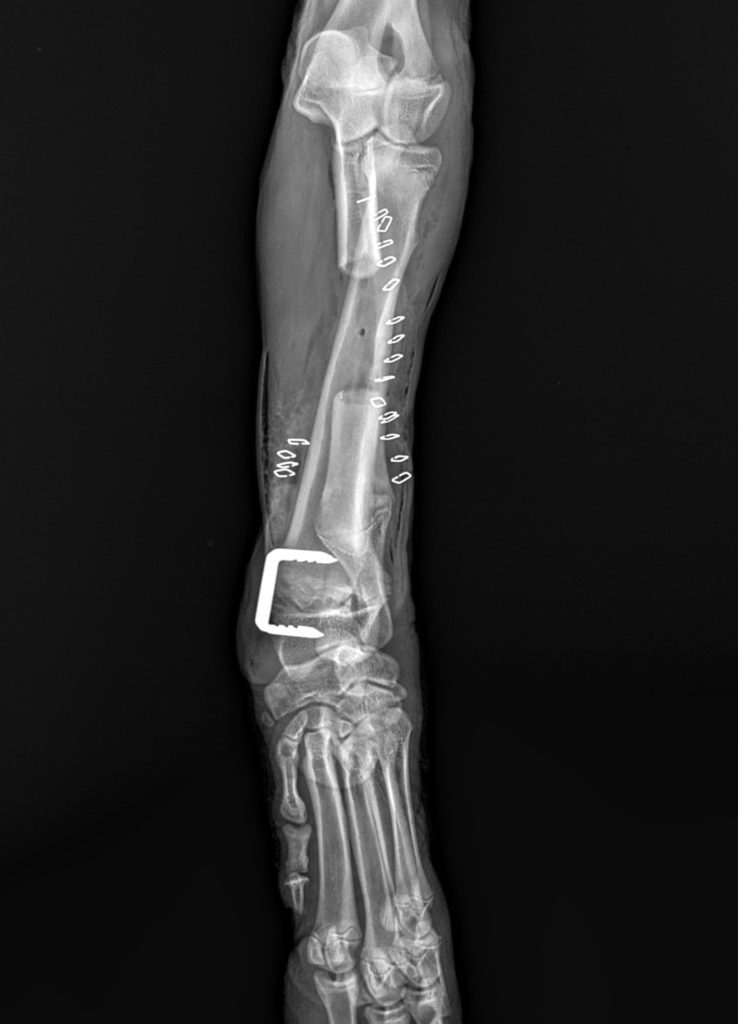

Poniżej prezentujemy zastosowanie klamer kostnych w leczeniu zespołu krzywej kości promieniowej u psa.

Zdjęcia przedstawiają osteotomię kości łokciowej i częściową epifizjodezę kości promieniowej.